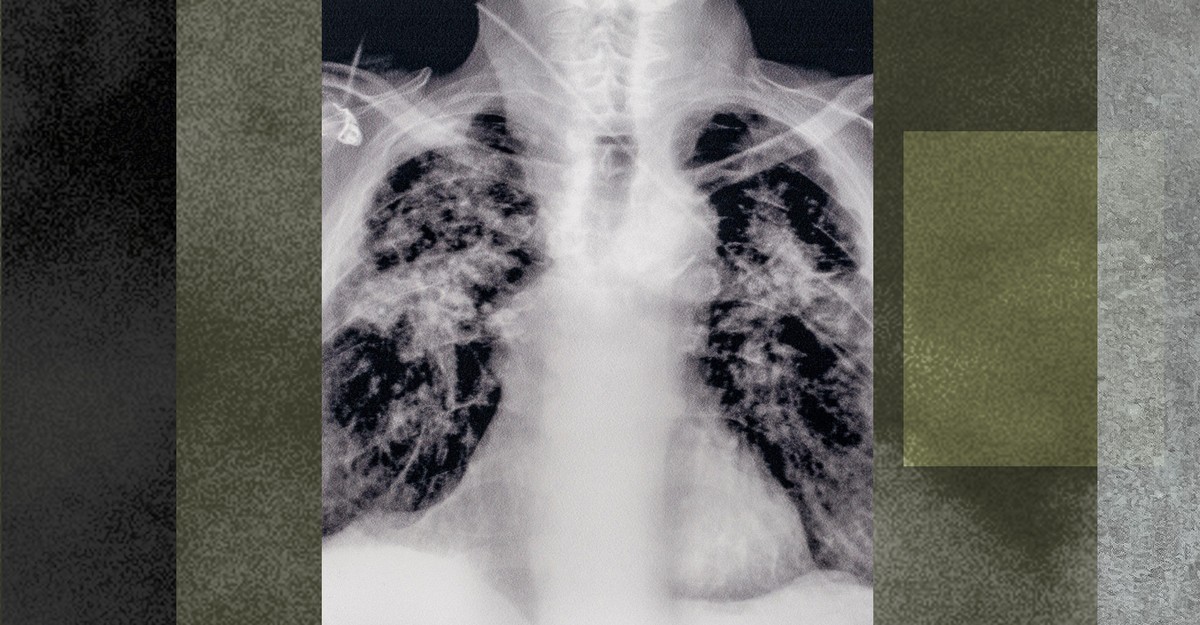

The worst workplace disaster in US history was silicosis.

Silicosis is no fucking joke. I watched my father die to fibrosis, which is very similar. He went from an energetic and active retiree to a chair bound and weak man in a matter of weeks. He lived the rest of his life barely able to walk from his car to the scooters to go grocery shopping. Doing so much as turning a valve to shut off the water to his sprinklers would have taken him an hour or more, and he wouldn’t have been able to do much else that day.

He lived for 2 of the 5 years he thought he had fighting for every single breath. All day. Every day.

Silicosis is typically caused by years of breathing in silica dust at work, and can worsen even after work exposures stop. In recent years, after decades of inaction, the federal government finally took several important steps to reduce the incidence of this ancient and debilitating disease. Under the Trump administration, all that progress is going away, in but one example of the widespread destruction now taking place across the federal government.